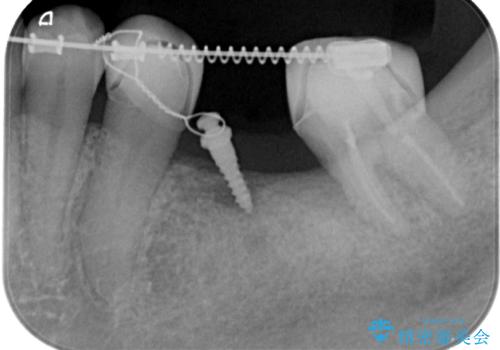

そのため、左下8を抜いて、左下7を部分矯正で後ろに起こしてからブリッジを新製することとしました。

最初にもともとのブリッジを壊し、矯正用の仮歯にかえた上で部分矯正を開始しました。

部分矯正期間はだいたい3か月弱です。